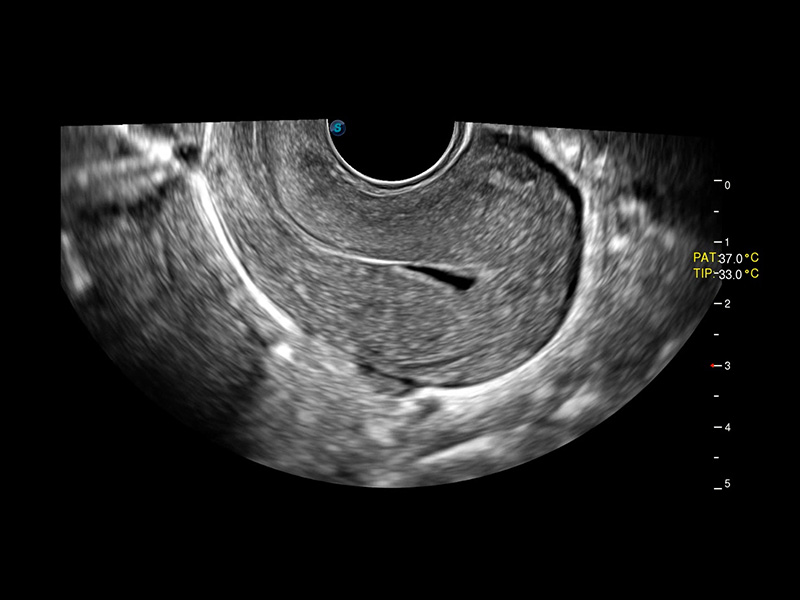

• IUD mit 3D-Rendering